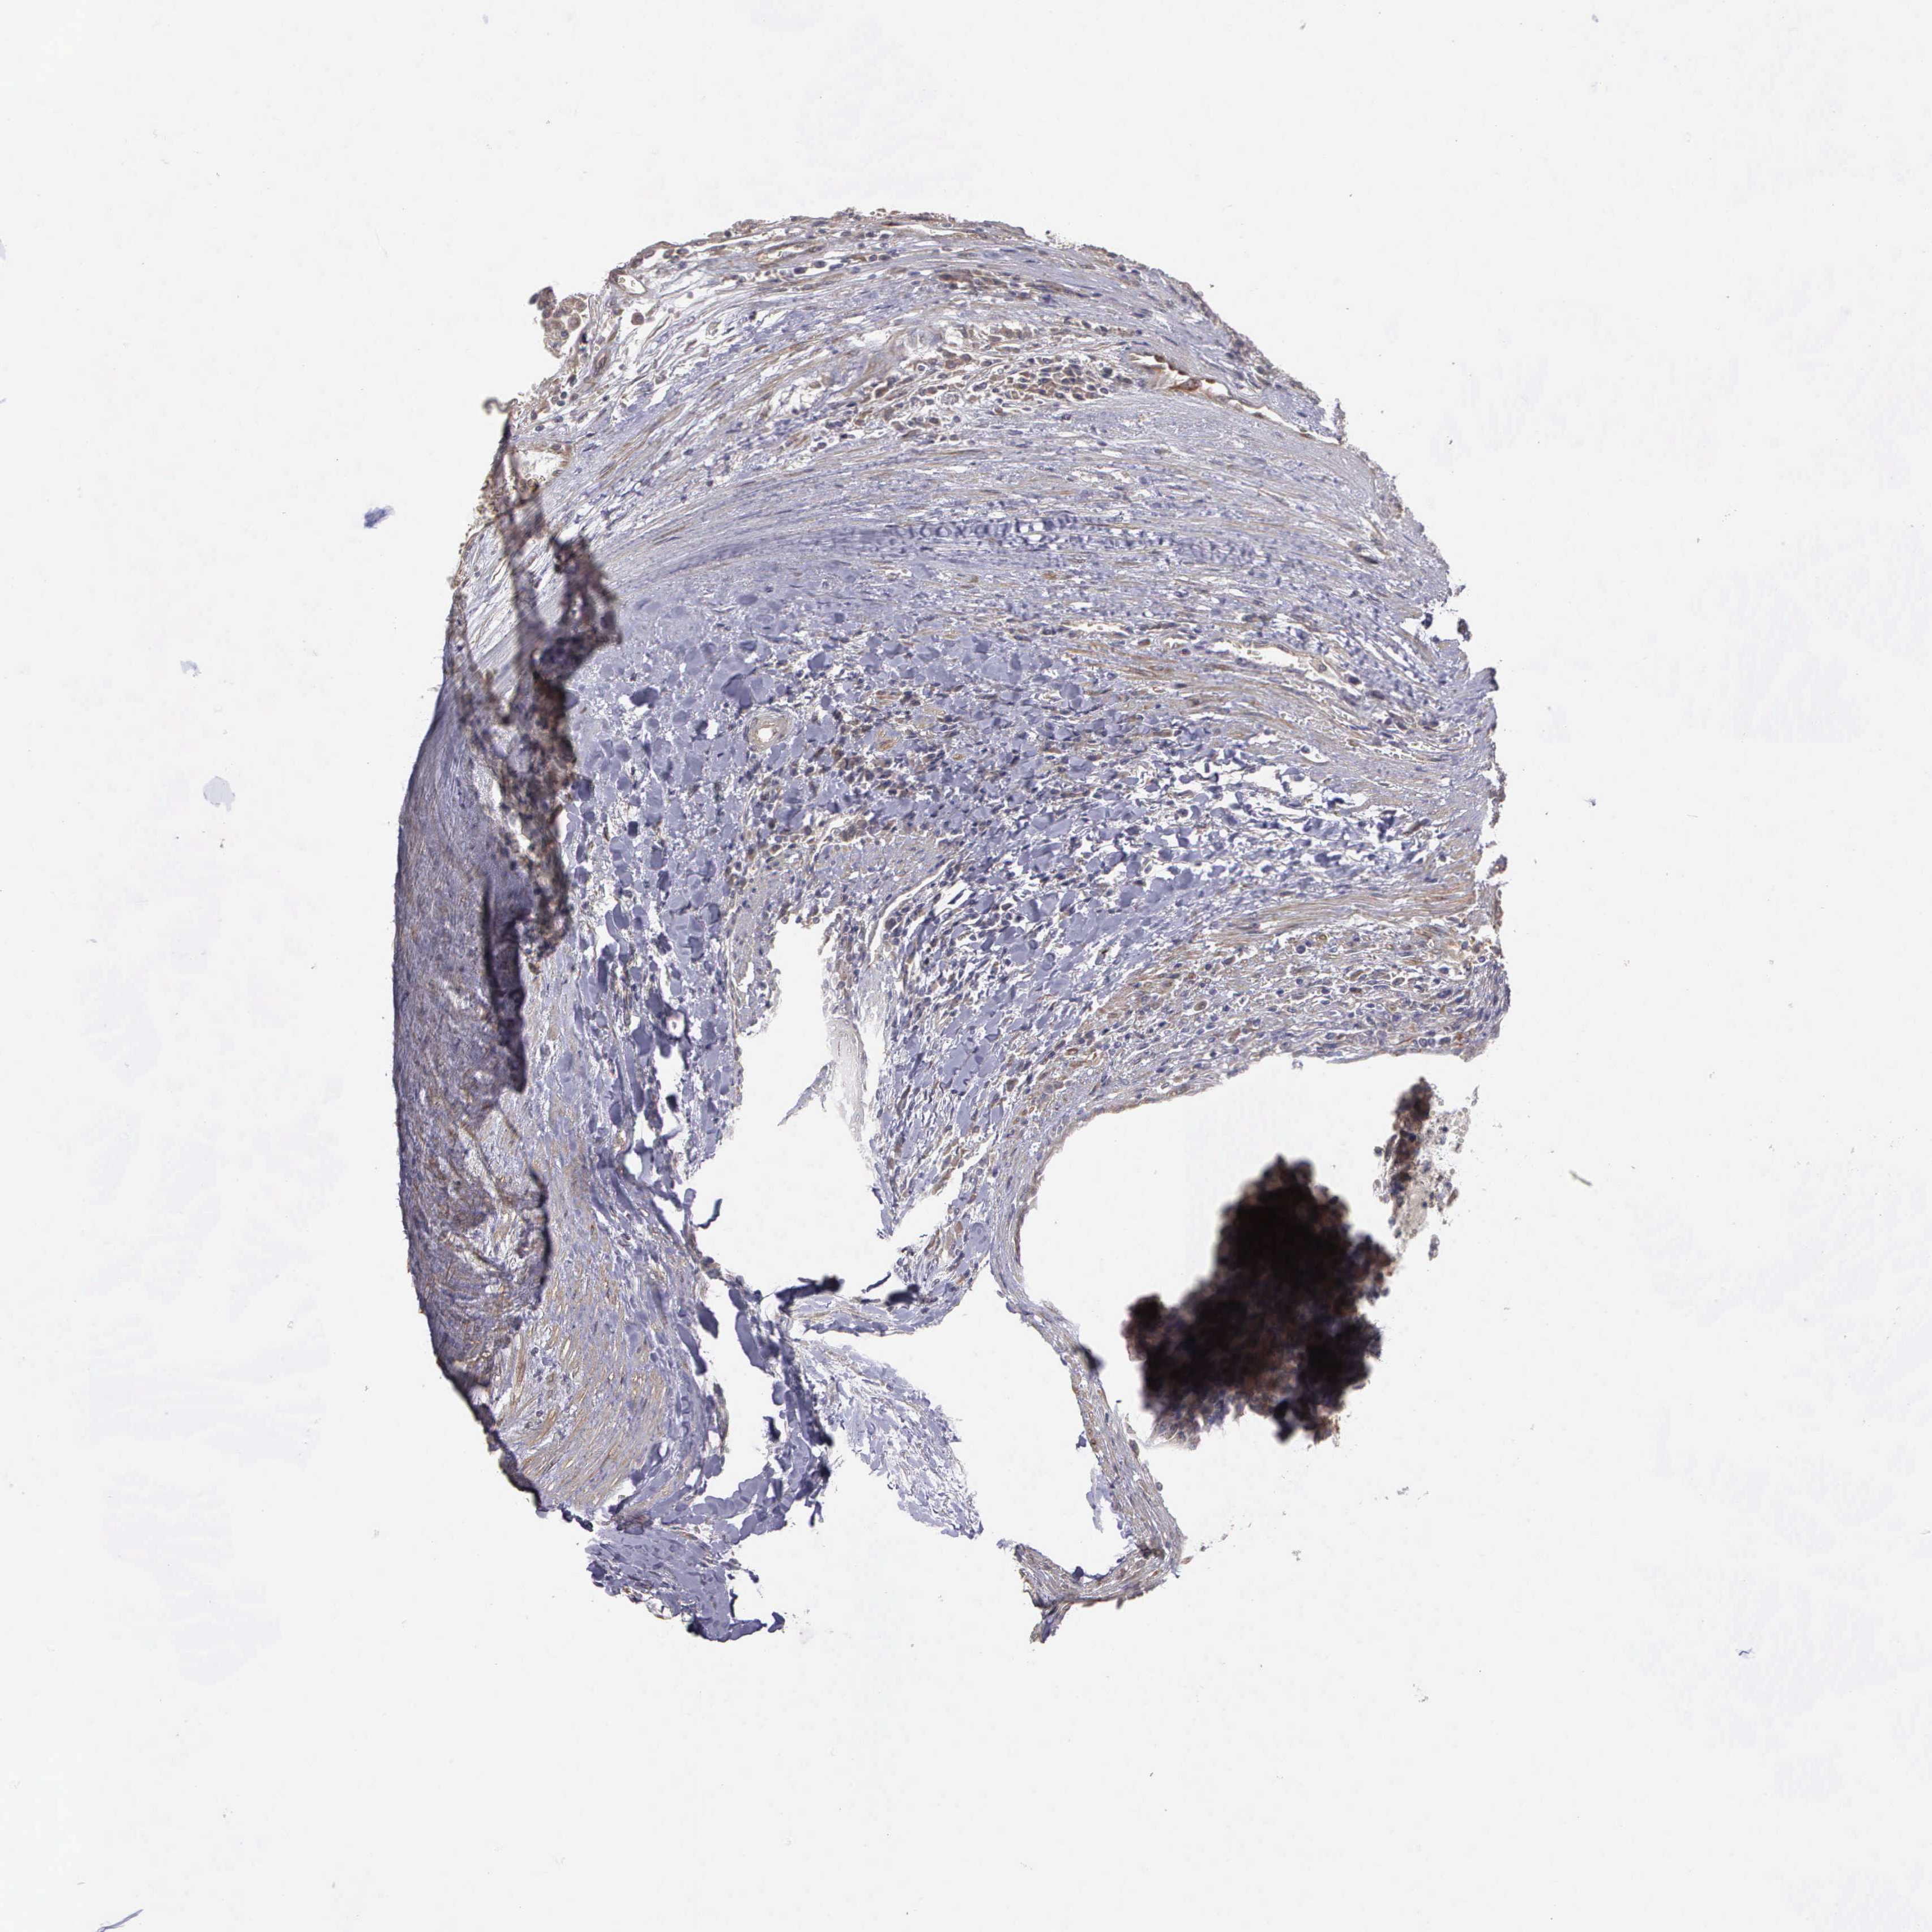

KIDNEY RENAL CLEAR CELL CARCINOMA (VALIDATION) - Interactive survival scatter ploti

The Survival Scatter plot shows the clinical status (i.e. dead or alive) for all individuals in the patient cohort, based on the same data that underlies the corresponding Kaplan-Meier plots. Patients that are alive at last time for follow-up are shown in blue and patients who have died during the study are shown in red.

The x-axis shows the expression levels (FPKM) of the investigated gene in the tumor tissue at the time of diagnosis. The y-axis shows the follow-up time after diagnosis (years). Both axes are complimented with kernel density curves demonstrating the data density over the axes. The top density plot shows the expression levels (FPKM) distribution among dead (red) and alive patients (blue). The right density plot shows the data density of the survived years of dead patients with high and low expression levels respectively, stratified using the cutoff indicated by the vertical dashed line through the Survival Scatter plot. This cutoff is automatically defined based on the FPKM cutoff that minimizes the p-score. The cutoff can be changed by dragging the vertical line or by entering a cutoff value in the square labeled "Current cut-off".

Under the Survival Scatter plot the p-score landscape (black curve; left axis) is shown together with dead median separation (red curve; right axis). Dead median separation is the difference in median mRNA expression between patients who have died with high and low expression, respectively. It is calculated as follows: median FPKM expression of dead patients with high expression - median FPKM expression of dead patients with low expression. This is intended to aid the user in visually exploring custom cutoffs and the associated p-scores and dead median separation.

Individual patient data is displayed and can be filtered by clicking on one or more of the category buttons on the top of the page. Categories describing expression level and patient information include: high, low, alive, dead, female, male and tumor stages. The scale of the x-axis can be toggled between linear and log-scale by clicking on the "x log" button. Mouse-over function shows TCGA ID, patient information and mRNA expression (FPKM) for each patient.

& Survival analysisi

Kaplan-Meier plots summarize results from analysis of correlation between mRNA expression level and patient survival. Patients were divided based on level of expression into one of the two groups "low" (under cut off) or "high" (over cut off). X-axis shows time for survival (years) and y-axis shows the probability of survival, where 1.0 corresponds to 100 percent.

RTL10 is not prognostic in Kidney Renal Clear Cell Carcinoma (validation)

Best expression cut offi

Based on the FPKM value of each gene, patients were classified into two groups and association between prognosis (survival) and gene expression (FPKM) was examined. The best expression cut-off refers the FPKM value that yields maximal difference with regard to survival between the two groups at the lowest log-rank P-value. Best expression cut-off was selected based on survival analysis .

When clicking on this number, the vertical dashed line indicating cut-off, the interactive survival plot, and the Kaplan-Meier curve will be adjusted to show results based on the best expression cut-off.

: 4.37

P scorei

Log-rank P value for Kaplan-Meier plot showing results from analysis of correlation between mRNA expression level and patient survival.

N/A

TCGA RNA samplesi

RNA-seq data is reported as average FPKM (number Fragments Per Kilobase of exon per Million reads), generated by the The Cancer Genome Atlas (TCGA) .

Normal distribution across the dataset is visualized with box plots, shown as median and 25th and 75th percentiles. Points are displayed as outliers if they are above or below 1.5 times the interquartile range. FPKM values of the individual samples are presented next to the box plot.

Average pTPM 3.9

Number of samples 100